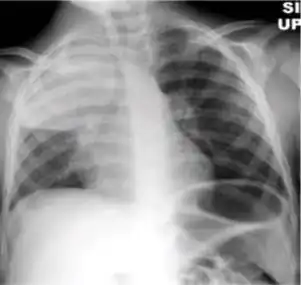

-

Chest x-ray showing dense opacity pleural effusion in the lower left lung of primary pulmonary TB.